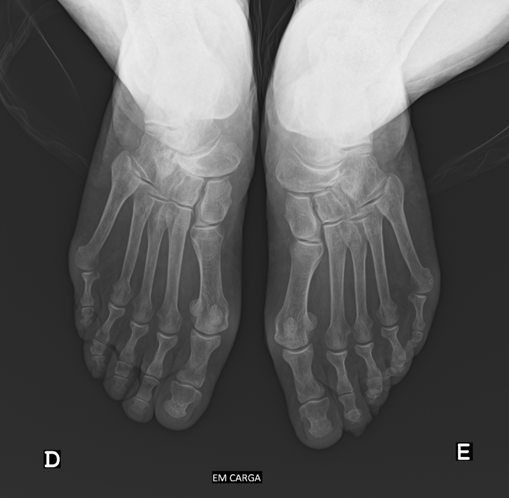

Geralmente o estudo é complementado com exames auxiliares de diagnóstico, como a radiografia dos pés em carga, onde podemos observar a fragmentação e colapso do navicular, o varismo do retropé e subluxação lateral do astrágalo. Pode ainda visualizar-se o estreitamento do espaço articular, esclerose do osso subcondral, formação de osteófitos e possíveis deformidades articulares. Pode ser necessário o estudo complementar com tomografia computorizada ou ressonância magnética.